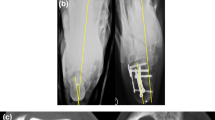

Knowledge and expertise in managing closed fractures of the calcaneus in adults has significantly increased over the past few years. Conservative management methods have been popular1, consisting of reducing the width of the calcaneus with use of a hammer, taking care to limit soft tissue trauma, followed by plantarflexion of the forefoot to restore the plantar arch. As this technique does not directly reduce the subtalar joint and requires immobilization in a plaster cast, post-traumatic osteoarthritis and joint stiffness are common complications of a conservative management2. With advancements in surgical techniques, open reduction and internal fixation with plates (ORIF), via an L-shaped lateral approach, has become the standard method for treating displaced, intra-articular calcaneal fractures3. ORIF provides a direct reduction of the articular facet of the calcaneus, which forms the subtalar joint and allows early mobilization. However, this open reduction technique is associated with a high risk of soft tissue complications related to the surgical wound, such as: hematoma formation, skin edge necrosis, wound breakdown and superficial or deep infection4. Recently, minimally invasive reduction and fixation has emerged as an alternative to ORIF to avoid soft tissue complications5. In recent years, the popularity of using percutaneous reduction and fixation with Kirschner wires (PRFK) as a minimally invasive treatment for calcaneal fractures has increased in China. This procedure usually consists of inserting a Kirschner wires (K-wire), using a joystick, from the calcaneal tuberosity to beneath the subtalar joint, with plantarflexion of the forefoot used to reduce the fracture. After the K-wire is advanced into the distal fracture fragment, augmentation fixation using one or two K-wires is necessary. However, there are no clear guidelines to inform the selection of either a PRFK or ORIF approach for the management of calcaneal fractures in adults. Therefore, we conducted a literature search to identify randomized controlled trials (RCTs) comparing PRFK and ORIF techniques and performed a meta-analysis with the intent of evaluating the evidence to inform selection of the preferred technique.

The post-operative Böhler’s angle was reported in 12 trials11,13,14,15,16,17,18,19,21,22,24,27, with analysis of the pooled data, shown in Fig. 6, indicating a MDs of −1.93° (95% CI, −3.97–0.11; P = 0.06). The post-operative angle of Gissane was reported in 10 trials11,13,14,15,16,17,18,19,21,22, with analysis of the pooled data, shown in Fig. 7, indicating a MD of −5.66° (95% CI, −8.49–−2.82; P < 0.0001).

In terms of calcaneal width, 5 trials reported their post-operative calcaneal widths13,14,15,18,22; the pooled data shown in Fig. 8, with a calculated MD of 1.42 mm (95% CI, 0.10–2.74 mm; P = 0.04). Post-operative calcaneal height was reported in 4 trials13,14,19,22, with the pooled data shown in Fig. 9, indicating a MD of −4.00 mm (95% CI, −6.59–−1.41 mm; P = 0.002).